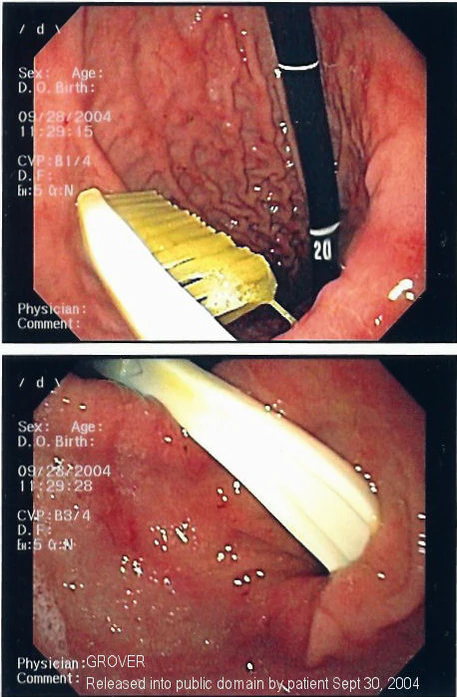

Иноро́дное те́ло (лат. corpus alienum) — с медицинской точки зрения любой чужеродный предмет, попавший внутрь организма. В узком смысле — посторонние предметы различных размеров, попавшие в глаз, ухо, нос, глотку, гортань, в пищевод или трахею (дыхательное горло), заноза.

Инородное тело, даже не повредив окружающие ткани, может стать причиной смерти. Например, в результате удушья, вызванного рефлекторным спазмом голосовых связок или непрофессиональных попыток извлечения инородного тела, приведших к гибели пациента[1], а также в результате контакта со слизистой (например, батарейка может вызвать химический ожог[2]). Дети могут засунуть мелкие предметы, например бусины, в нос или ухо[3]